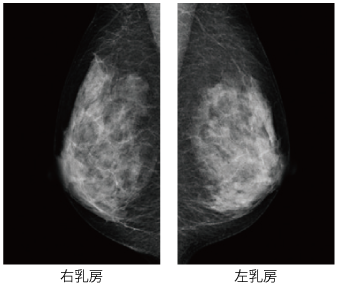

乳房撮影検査(マンモグラフィ)とは

乳房のエックス線撮影のことです。乳房の特徴を考慮した専用の装置を使用します。通常、乳房全体が撮影フィルムの中に全て写し出されるように、複数の方向から撮影を行います。触っても判らないような小さな乳がんはもちろん、しこりをつくらない乳がんを白い影や非常に細かい石灰化の影として写すことができます。